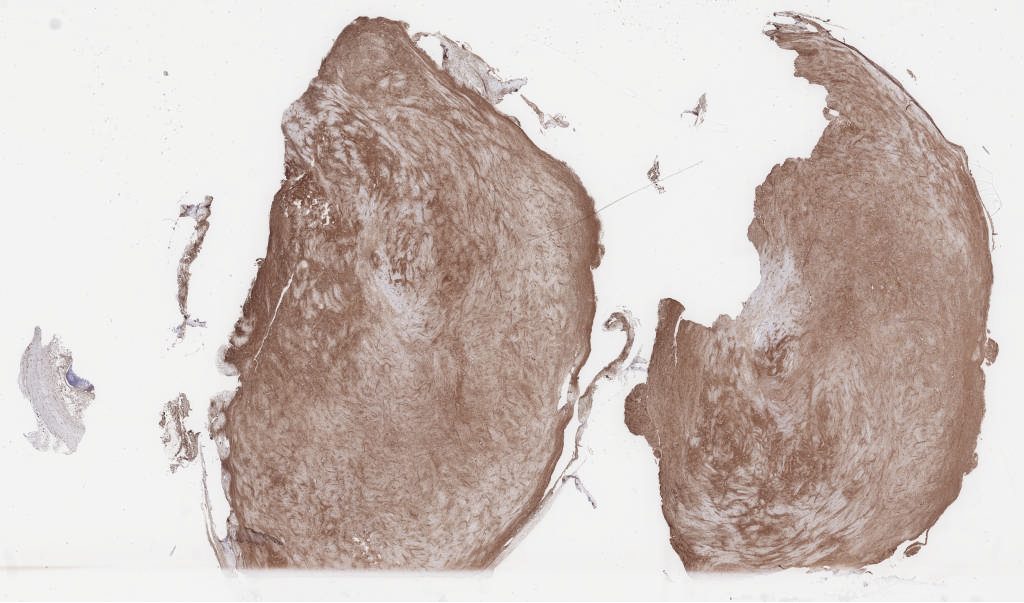

sma.svs

139440

x

93983

@

40X